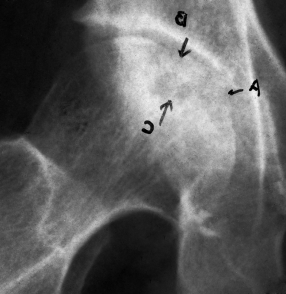

病例10 女,55岁,双侧锁骨骨纤维异样增殖症5年,疼痛严重,经治疗6个月痊愈.

Case 1, female, 55 years old, bone fiber dysplasia for 3 years, severe pain, cured after eating for 6 months. Before eating, the clavicles, sternum and the first rib on both sides were thickened and deformed, with uneven density (a). After eating, the density of clavicle, sternum and the first rib on both sides were more uniform than before (b).